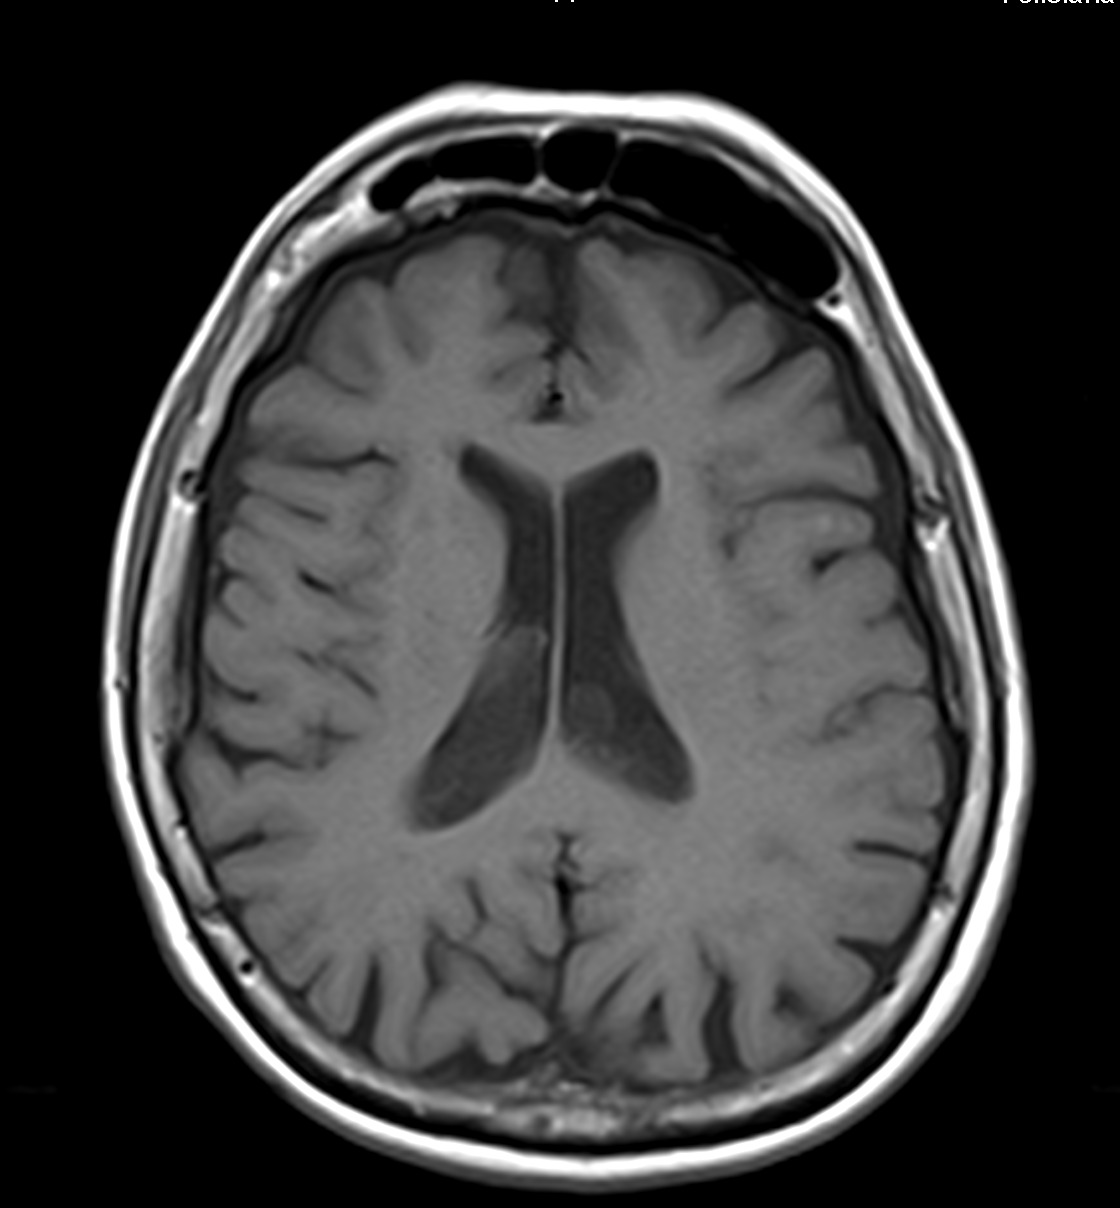

✔ Lesiones intraventriculares

✔Bilaterales

✔65% restringen en la secuencia de difusión

✔ Realce variable posterior a la administración de medio de contraste

✔ No hay edema del parenquima adyacente

NO DEBEN CONFUNDIRSE CON LESIONES TUMORALES INTRAVENTRICULARES!!!!